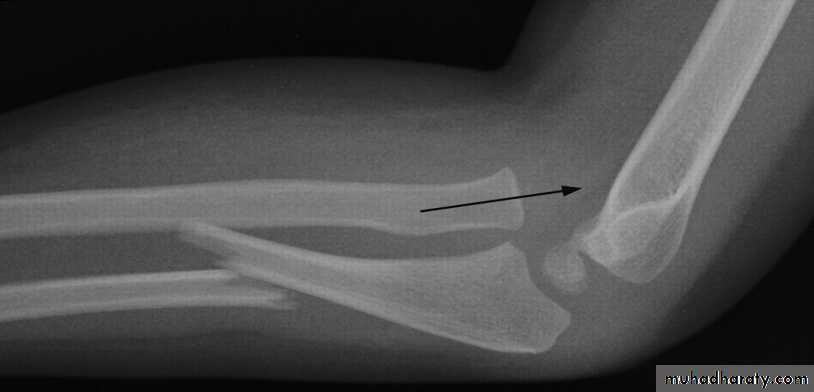

Monteggia fracture dislocation of the ulna

It is fracture of the proximal third of the ulna with dislocation or subluxation of the proximal radio- ulnar joint .

Clinically : the ulnar deformity is usually obvious but the dislocated head of radius

is masked by the swelling .

X-ray : in isolated fracture ulna it is essential to take true a-p and lateral views of

the elbow ; the normal radial head is usually pointing to wards the capitulum in

monteggia it is not ; in addition to appearance of the fracture .

Montegia fracture dislocation